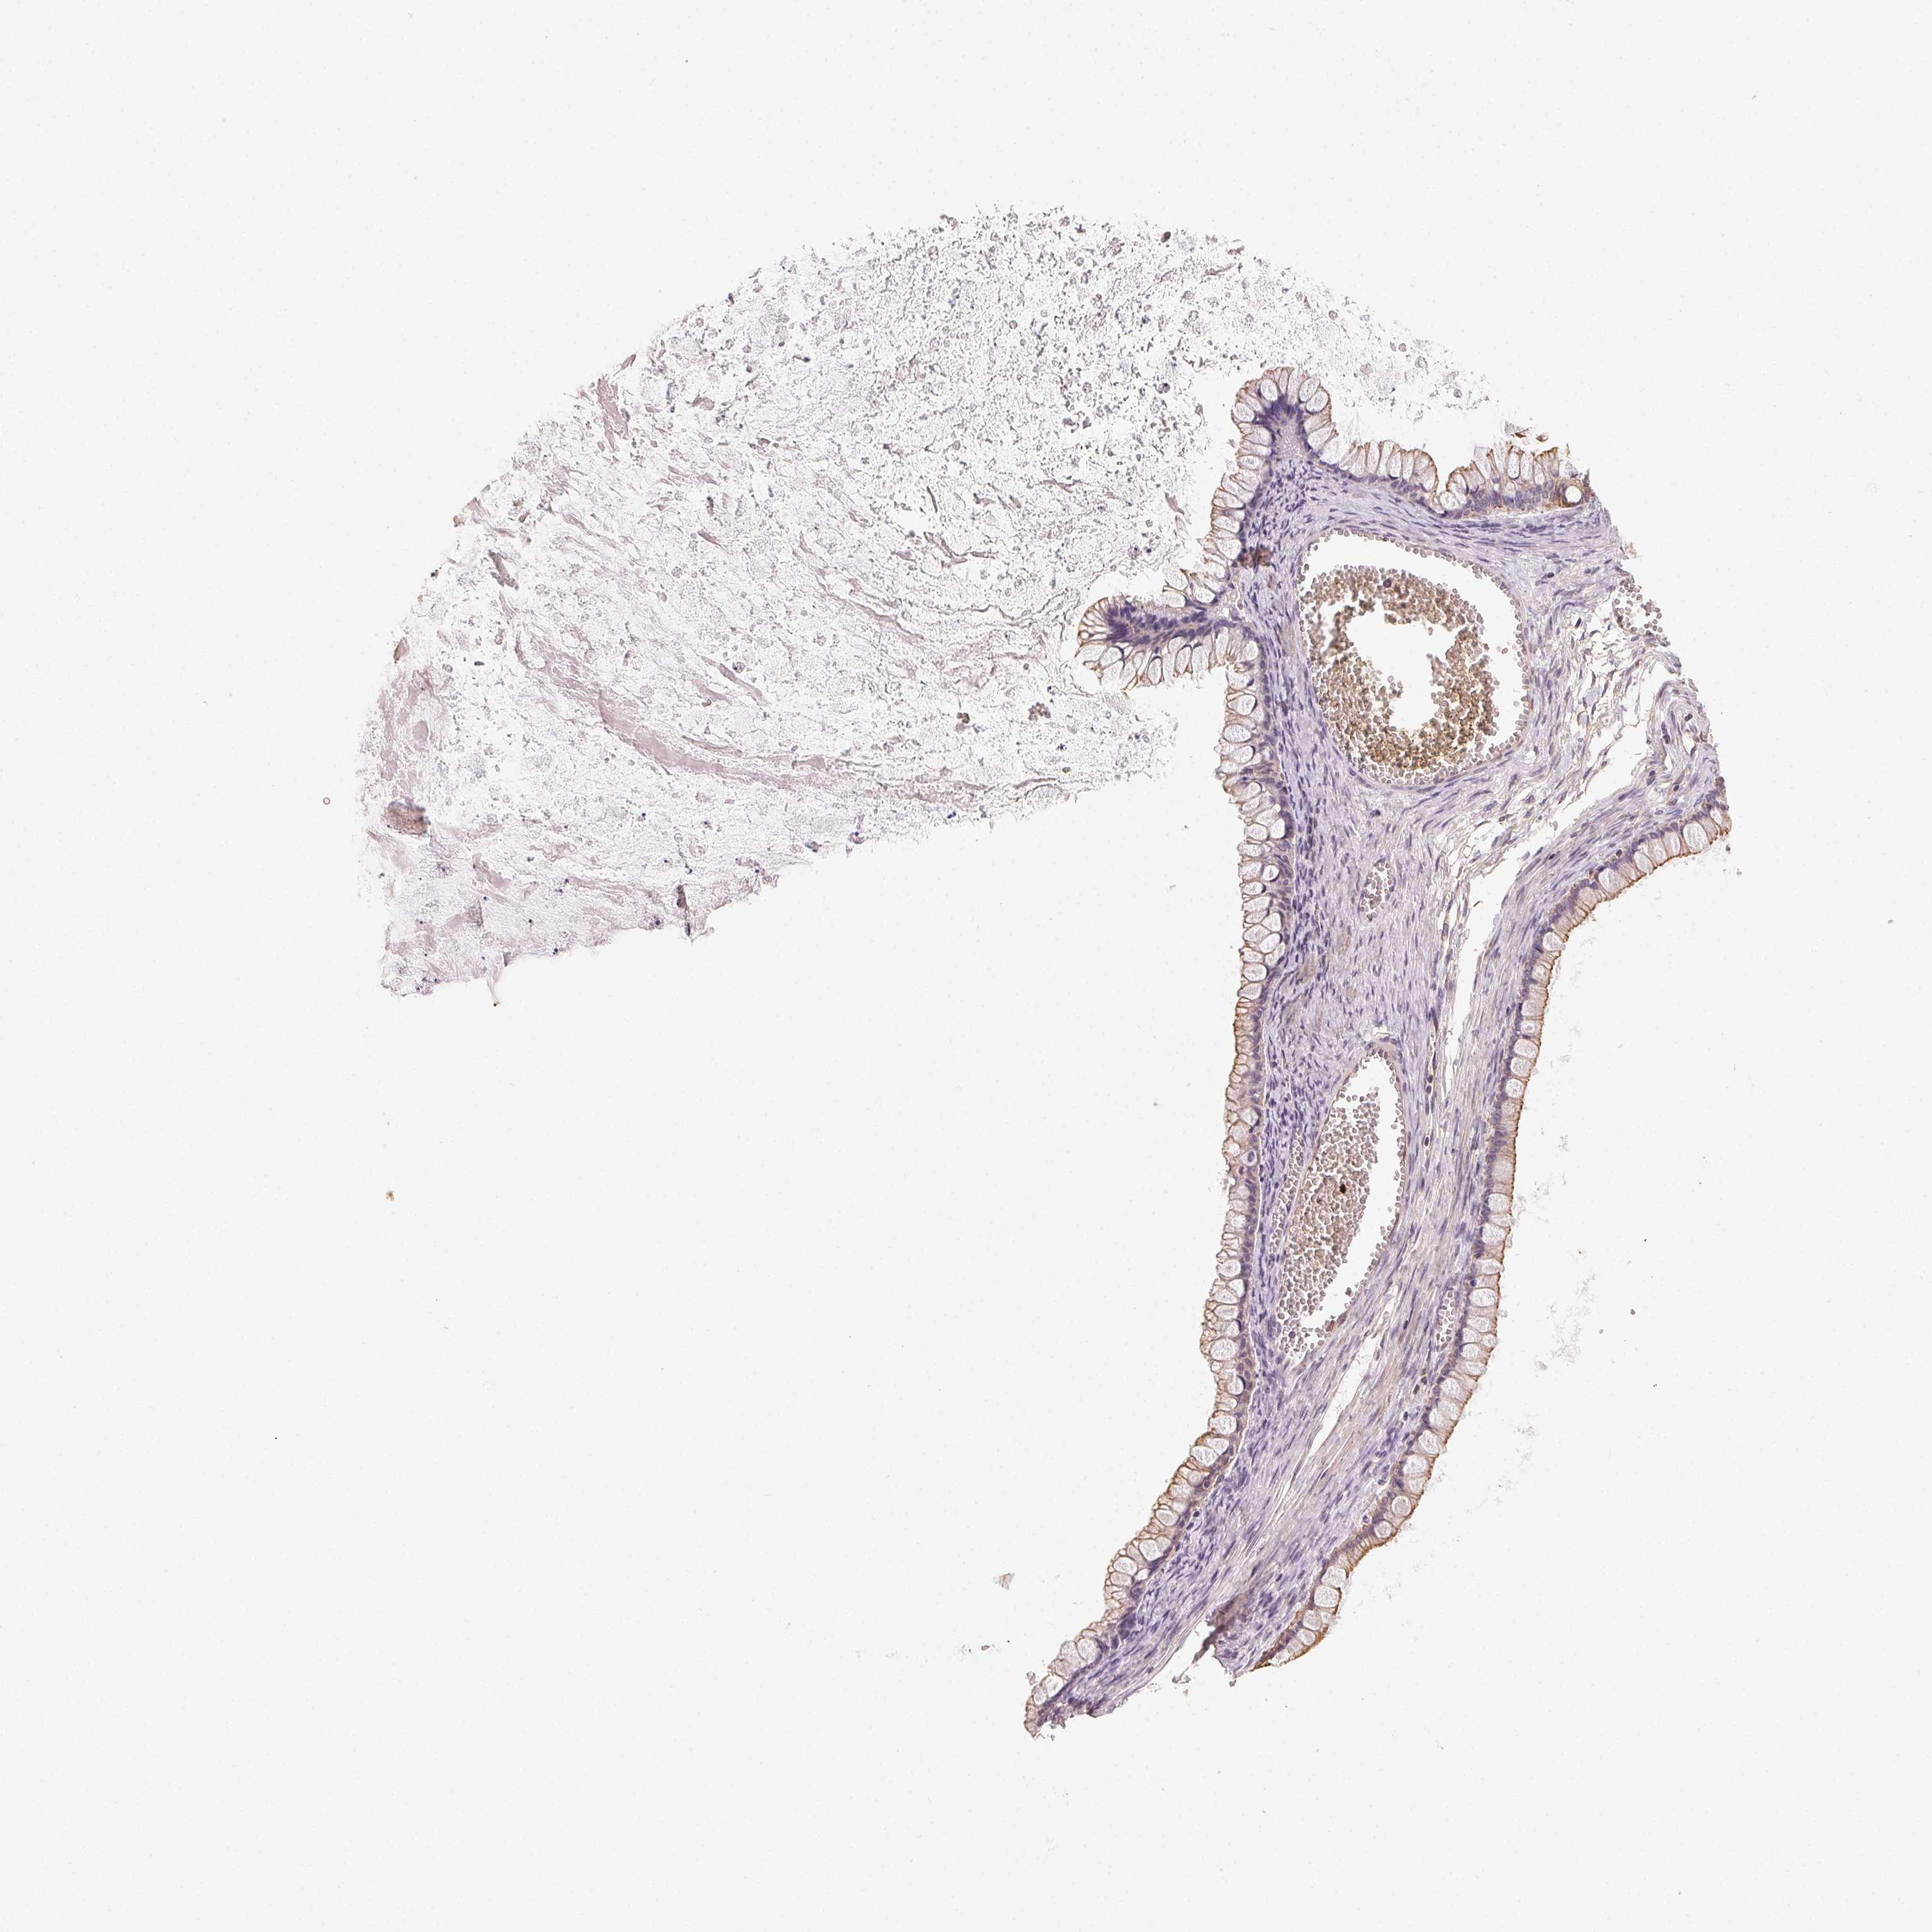

OVARIAN CANCER - Protein expressioni

A mouse-over function shows sample information and annotation data. Click on an image to view it in a full screen mode. Samples can be filtered based on level of antibody staining by selecting one or several of the following categories: high, medium, low and not detected. The assay and annotation is described here.

Note that samples used for immunohistochemistry by the Human Protein Atlas do not correspond to samples in the TCGA dataset.

Antibody stainingi

Antibody staining in the annotated cell types in the current human tissue is reported as not detected, low, medium, or high, based on conventional immunohistochemistry profiling in selected tissues. This score is based on the combination of the staining intensity and fraction of stained cells.

Each image is clickable and will lead to virtual microscopy that enables deeper exploration of all samples and also displays staining intensity scores, fraction scores and subcellular localization as well as patient and tissue information for each sample.

Antibody HPA056752

Staining

High

Medium

Low

Not detected

Intensity

Strong

Moderate

Weak

Negative

Quantity

>75%

75%-25%

<25%

None

Location

Nuclear

Cytoplasmic/membranous

Cytoplasmic/membranous,nuclear

Cystadenocarcinoma, serous, NOS

Cystadenocarcinoma, mucinous, NOS

Carcinoma, endometroid